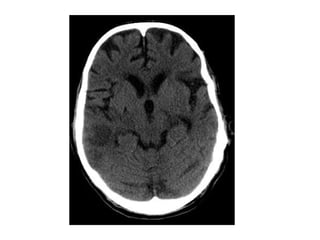

Patient with acute vision loss in the right half of the visual field ,

CT shows an infarction in the contralateral visual cortex , i.e

left occipital lobe

PCA infarction , notice the loss of gray / white matter differentiation in

the region of the left occipital lobe